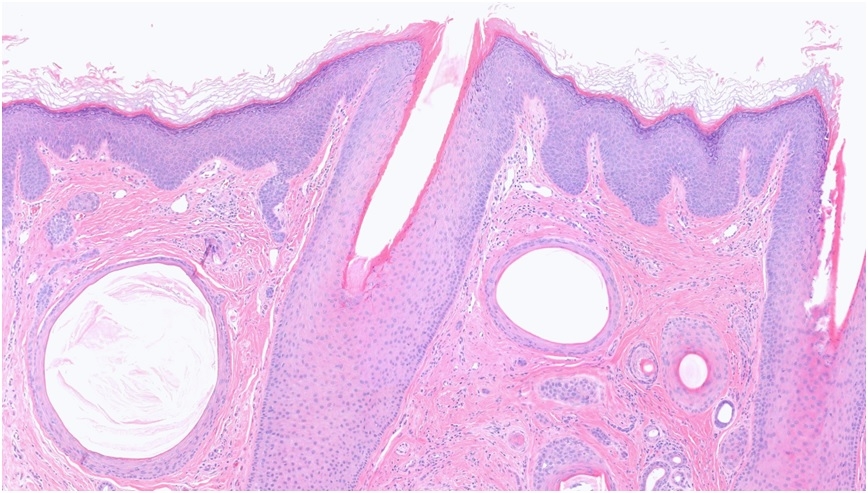

29M, Right side chin, punch excision 6 mm ?Cyst inflamed

WSI revealed areas that looked like trichoadenoma

Superficial aspect looks like trichoadenoma, but there is also a deeper component... ? desmoplastic trichoepithelioma ?MAC.

I am worried about MAC in this case.

PMB-like stroma. Favour Desmoplastic TE.

Trichoepithelioma